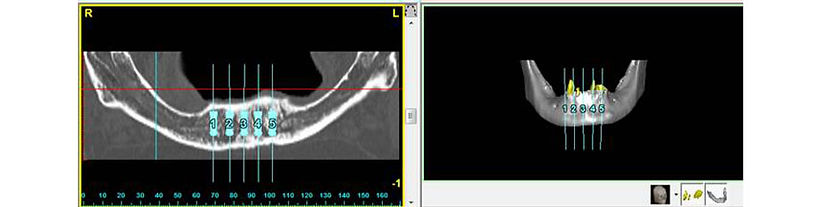

An unhappy patient with the esthetics of the upper denture and lower hopeless dentition. With 3-dimensional planning, implants were placed the same day teeth were extracted and a fixed-non removable provisional was delivered. After 3 months, the implants were integrated into the bone, the final prosthesis completed and a new denture was delivered so the patient could properly eat and smile.

An unhappy patient wearing a full upper denture was frustrated with the denture and esthetics. A conversion when implants were placed, the same day had the full upper arch restored with screw-retained provisional. After 4 months, the final upper prosthesis was completed.